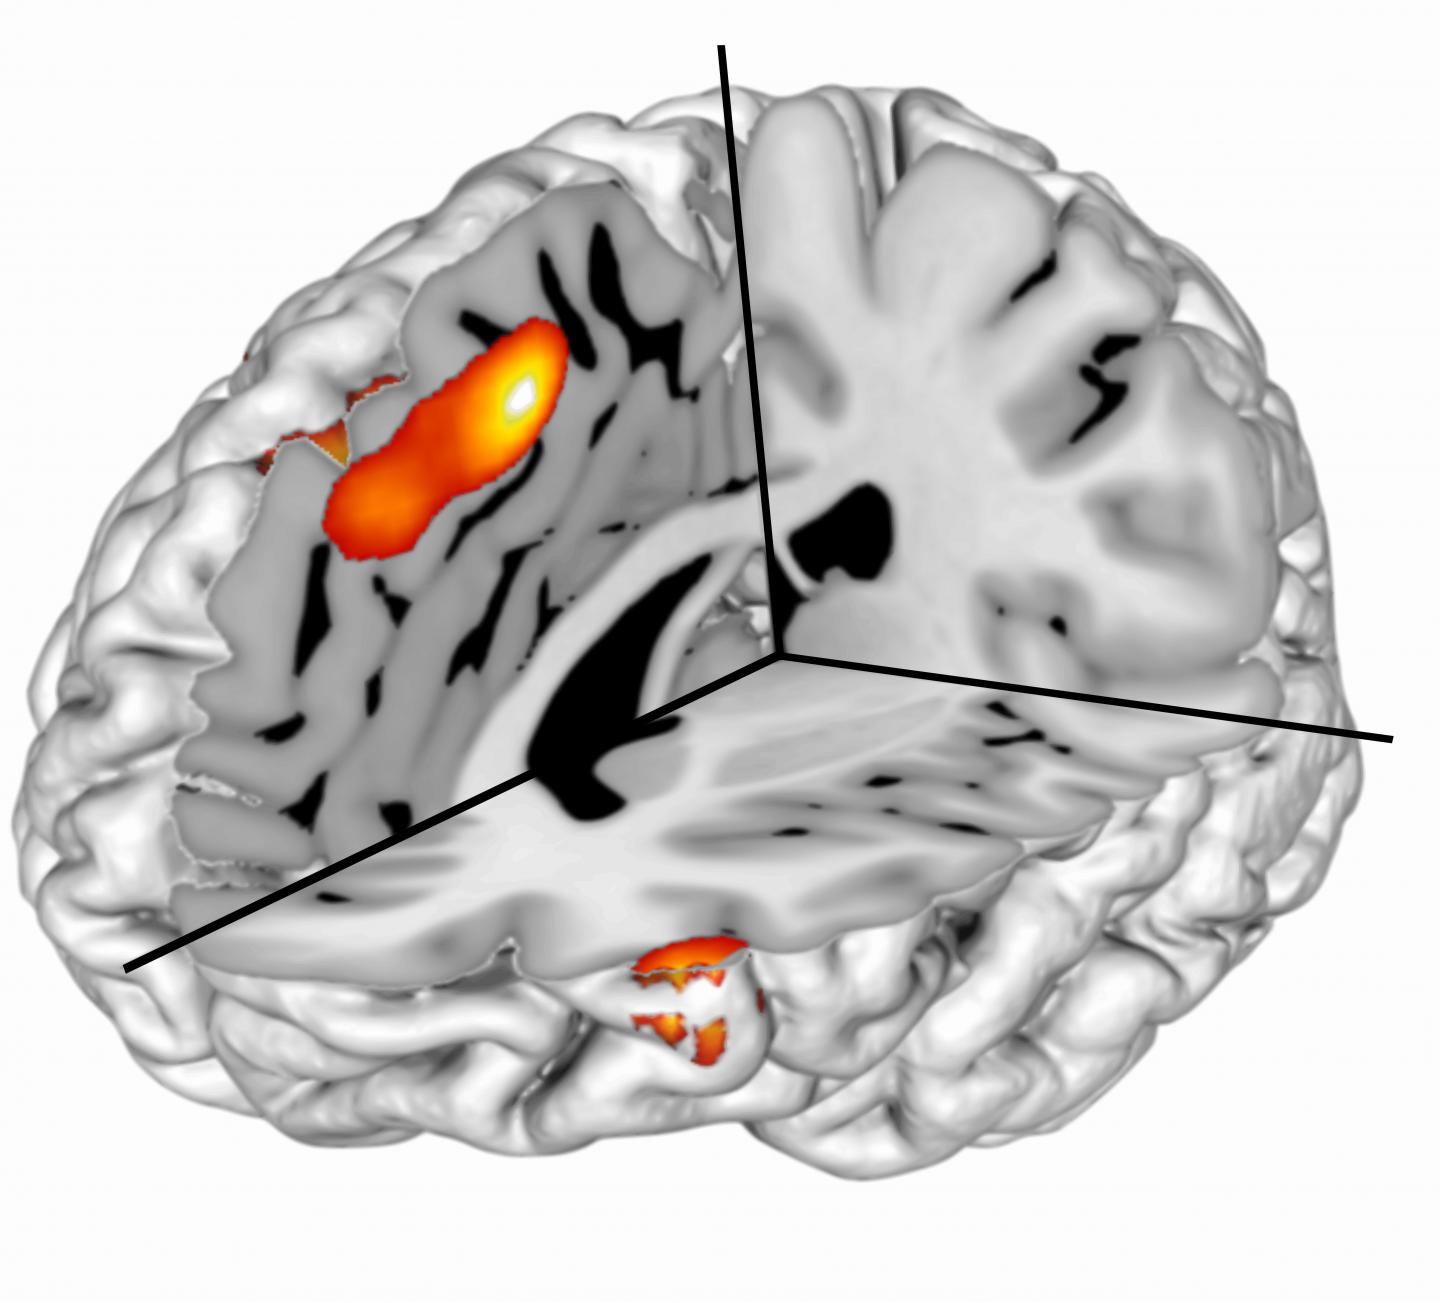

image: The orange section shown in the fMRI image of the brain is the region in the dorsal anterior cingulate cortex (dACC) researchers identified in their study. Activity in the dACC signals surprising events during motivated behavior.

Humans control their behavior in numerous ways, from stopping the urge pick at a scab to resisting the impulse to eat an entire box of chocolates. Suppressing undesired behavior, referred to as "cognitive control," traditionally has been linked to the functioning of the dorsal anterior cingulate cortex (dACC) in the front of the brain. Activity in dACC is observed across a variety of contexts, yet its function remains intensely debated in the field of cognitive neuroscience.

Researchers discovered that the single mechanism of surprise - defined in the paper as the difference between events that are expected to happen versus those that actually happen - best accounts for activity in dACC during a task requiring motivated control. The series of analyses they performed indisputably supported the PRO model - indicating that recognizing surprising events could provide a unified explanation for dACC function. Surprise signaling is the shared driver of inhibitory and motivated control and supports surprise coding as the core mechanism underlying medial prefrontal cortex function more generally, with the source of the surprise determining the exact neural population implicated.